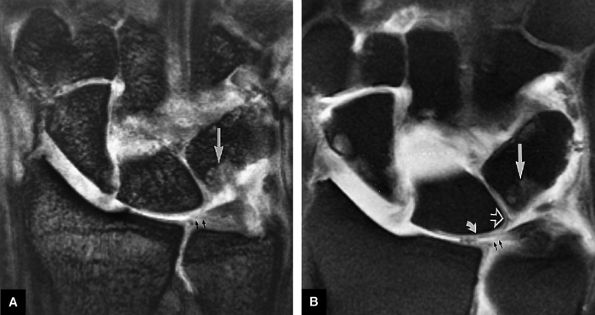

FIGURE 10.73 ● Anatomy of the scapholunate ligament complex on three separate coronal images. (A) Volar component. (B) Membranous component. (C) Dorsal component. (D) On a corresponding axial image all three components of the scapholunate ligament complex are demonstrated. The dorsal scapholunate ligament is horizontally oriented and is perpendicular to the joint. The fibers of the membranous portion of the scapholunate ligament course peripherally and obliquely from the scaphoid downward toward the lunate in a dorsal-to-volar direction. The volar scapholunate ligament courses obliquely from the scaphoid downward to the lunate. This arrangement of scapholunate ligament fibers biomechanically hinges the joint dorsally at the level of the dorsal transverse fibers. In forced extension, scapholunate ligament failure initiates in its volar aspect. S, scaphoid; L, lunate; v, volar component; m, membranous component; d, dorsal component. Arrows correspond to the course of each component of the scapholunate ligament.

|